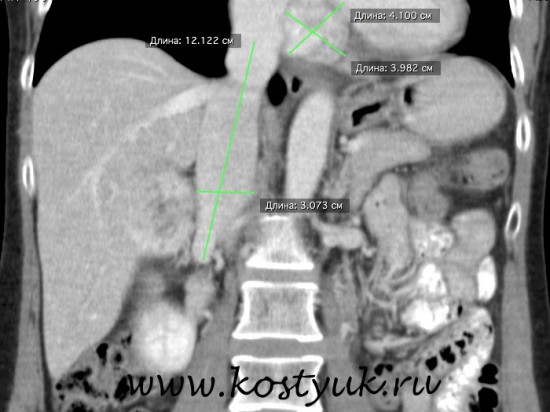

О лечении ПОЛИПОВ

Эндоскопическая профилактика рака

О полипах толстой кишки

Полипы и аденомы по своей сути являются опухолями кишечника.23.06.25

Клиническое наблюдение >>>